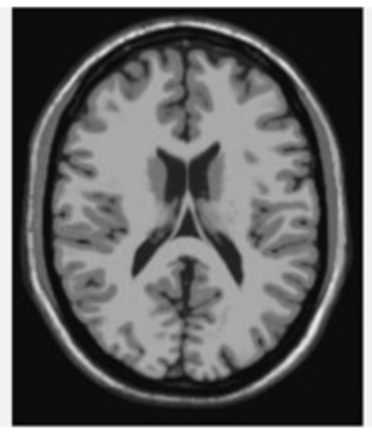

📊 그림 설명

T1-가중 MRI 뇌 스캔 이미지이다. CT에 비해 공간 해상도가 우수하여 회백질(회색)과 백질(밝은 색)을 명확히 구분할 수 있다. T1-가중 영상은 주로 구조적 뇌 영상에 사용되며, 뇌 주름(이랑)의 세부 구조까지 식별할 수 있다.

An example of CT (le), T1-weighted MRI (center), and T2-weighted MRI (right) scans of the brain. Note how the MRI scans are able to distinguish between gray maer and white maer. On the T1 weighted scan (normally used for structural images), gray maer appears gray and white maer appears lighter.

Different types of image can be created from different components of the MR signal. Variations in the rate at whi the protons return ba to the aligned state following the radio frequency pulse (called the T1 relaxation time) can be used to distinguish between different types of tissue. ese T1 weighted images are typically used for structural images of the brain. In a T1-weighted image, gray maer looks gray and white maer looks white. When in the misaligned state, at 90 degrees to the magnetic field, the MR signal also decays because of local interactions with nearby molecules. is is termed the T2 component. Deoxyhemoglobin produces distortions in this component and this forms the basis of the image created in functional MRI experiments (called a T2* image, “tee-two-star”).